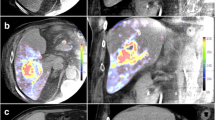

PBV-based C-arm CT was feasible in all patients and provided diagnostic quality in all cases. All HCC typical lesions (64/64, lesion diameter >10 mm) detected in pre-interventional imaging have been identified in PBV maps (κ = 1, p = 1.0) (Fig. 1). 49/64 lesions were detected in conventional angiography (κ = 0.77, p = 0.001). A total of 90 tumour feeding vessels were detected in PBV maps and arterial phase C-arm CT compared to 64 vessels in conventional angiography (κ = 0.71). This represents a median of 3 (range 2 to 4) tumour feeding vessels detected by PBV maps compared to a median of 2 (range 1 to 3) tumour feeding vessels seen in conventional angiography (p < 0.0001) (Fig. 2). All detected vessels were verified by super selective angiography. No additional tumour feeding vessels were seen in the super selective approach. Detailed information about number of tumour feeders and lesions in C-arm CT and corresponding angiogram are summed up in Table 2.

a Angiographic overview shows a hypervascularised HCC lesion in Segment VII (white line) with multiple tumour feeders (white arrows). Extent and location of tumour feeders is confusing. The black arrow marks the right hepatic artery. b–d 2D coronar (b, c) and 3D (d) PBV map reconstructions after C-arm CT acquisition facilitates analysis of location and extent of tumour feeding vessels